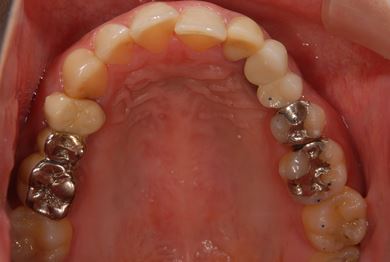

| 性別/年齢 | 女性 / 29歳 | ||||||||||||||||||||||||||||||||

| 治療方針 | 抜歯と同時にインプラント埋入を行い、治療期間を短縮する。 | ||||||||||||||||||||||||||||||||

| 治療内容 | インプラント2本(抜歯即日スピードインプラント)、ハイブリッドセラミッククラウン3本 | ||||||||||||||||||||||||||||||||